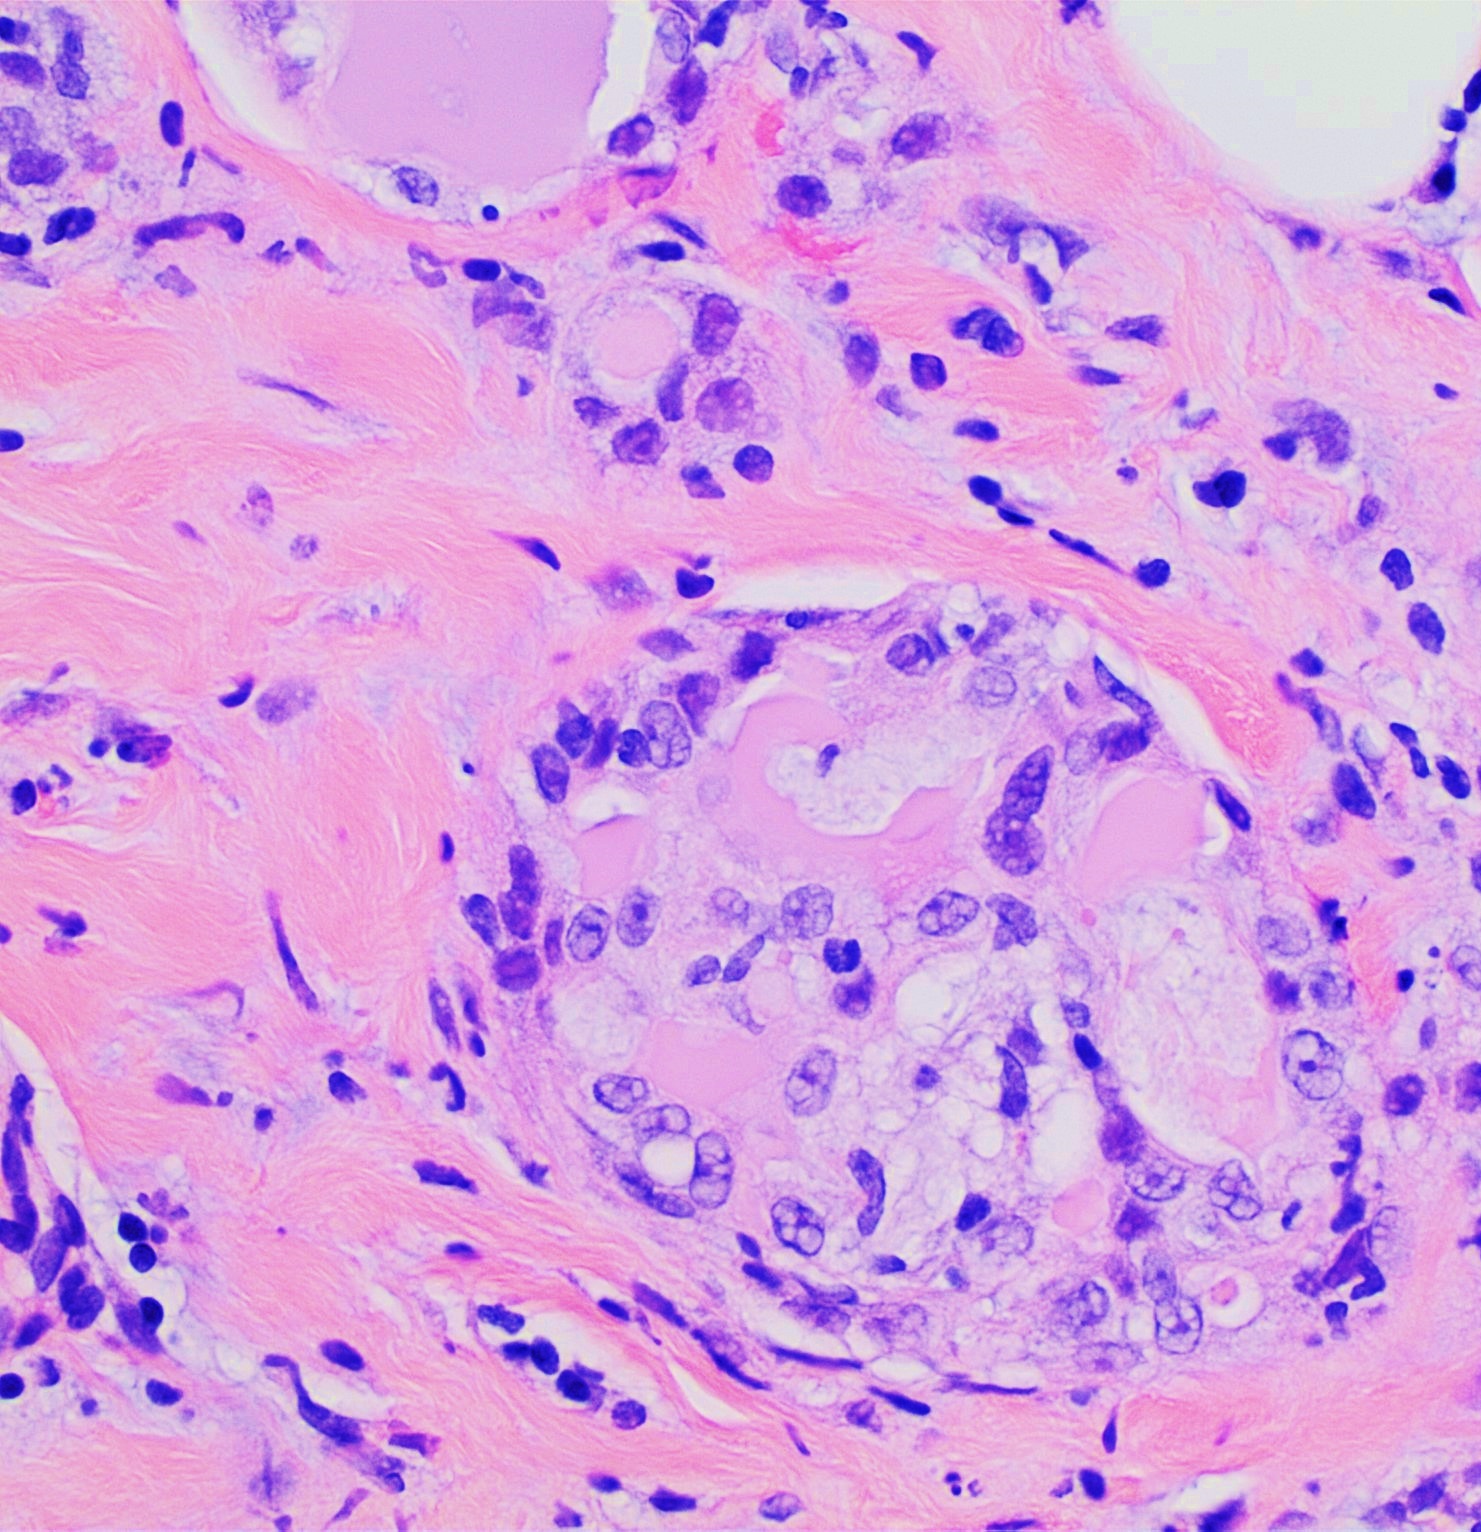

분비성 유방암(MSC) 종양을 H&E 염색하여 현미경으로 관찰하면, 일반적으로 경계가 명확한 고형 종양 형태로 나타난다. 이 종양은 다수의 미세낭포[13], 세포질 내에 수많은 공포를 가진 상피 세포 시트, 하나의 큰 세포질 공포를 가진 도장 세포, 그리고 세포 외 액적과 같은 분비물을 특징적으로 포함한다.[2] 이러한 세포 시트는 결합 조직 띠로 분리되어 있다.[5] 때로는 종양 세포가 손가락 모양의 유두상(papillary)[17] 또는 관 모양의 관상(tubular)[14] 패턴으로 배열되기도 한다.

세포 외 미세낭포와 세포 내 공포 및 구체는 H&E 염색에서 붉게 염색되며, 황산화된 글리코사미노글리칸과 뮤신 함유 물질로 구성되어 있다.[4] 이는 주기산-쉬프(PAS), PAS-디아스타제, 또는 알시안 블루와 같은 특수 염색을 통해 확인할 수 있다.[15] '분비성'이라는 명칭은 종양 세포의 공포와 구체가 세포 밖으로 분비되어 조직에 미세낭포 형태를 부여하는 특징에서 유래했다.[8] 드물게 종양 일부에서 육종과 유사한 악성 세포 변화가 관찰되기도 하며, 이는 빠른 전이를 동반하는 경향이 있다.[18][19] 또한, 순수하게 "제자리암"(즉, 유방의 관 외부에 있는 조직을 침범하지 않은 완전히 국소화된 종양) 형태로 발견된 경우는 매우 드물며, 보고된 사례들은 최소한 일부에서 유두상 구조를 보였다.[16]